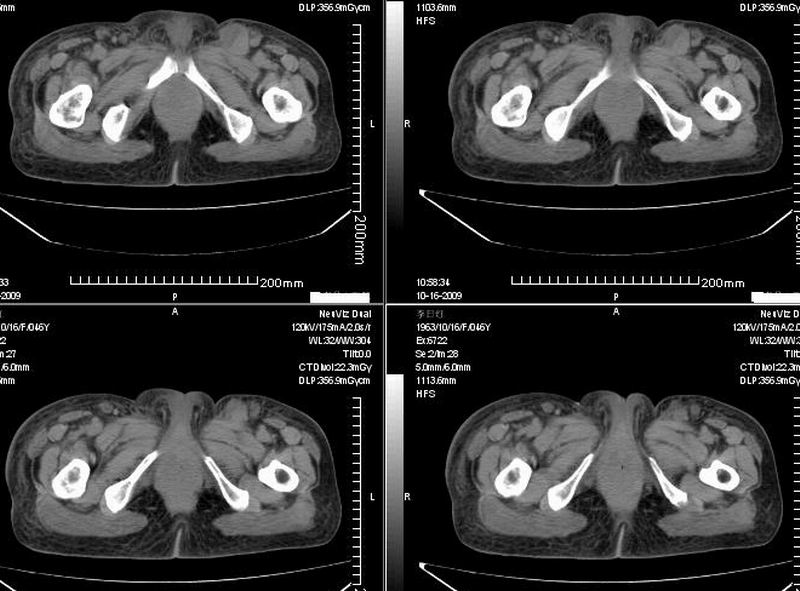

女:46y:一年前宫颈癌术后,现右下腹抚及肿块。

考虑宫颈癌术后复发周边侵犯/右中下腹及双侧腹股沟淋巴结转移。

考虑宫颈癌术后复发周边侵犯并右中下腹转移灶及双侧腹股沟淋巴结转移。